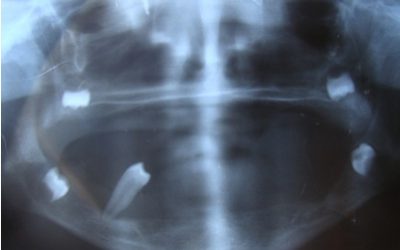

انتقاء الأسنان الاصطناعية وتنضيدها في الأجهزة الجزئية Selection and Arrangement of Artificial Teeth تصنيف عام